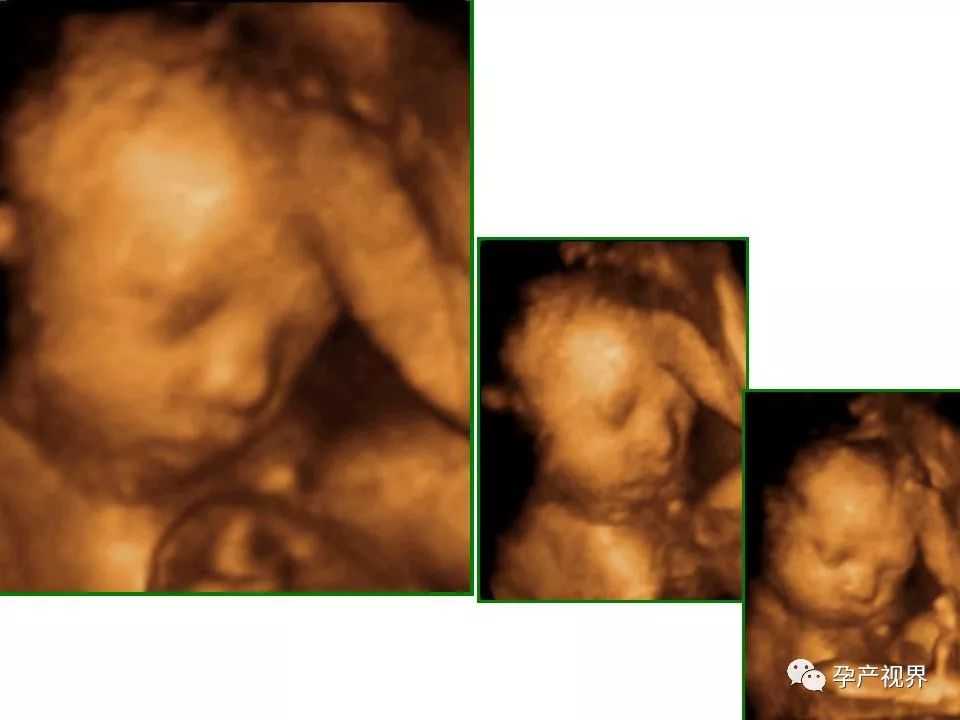

第3次产检项目中最重要的是B超筛查胎儿畸形,主要是看胎儿外观发育上是否有较大问题。医生会仔细测量胎儿的头围、腹围、看大腿骨长度及检查脊柱是否有先天性异常。如果准妈妈照的是四维彩超,还可以看到宝宝的实时面部表情。做彩超之前,要保持心态平和,如果过于紧张会影响到胎儿的活动哦。